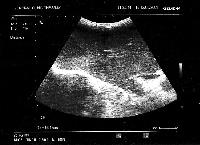

Δεξιά πλάγια ηπατεκτομή για συμπτωματικό φλεγμονώδη ψευδοόγκο

Πρόκειται για άνδρα ασθενή 50 ετών, ο οποίος υποβλήθηκε σε αξονική τομογραφία άνω κοιλίας στα πλαίσια διερεύνησης πυρετού αγνώστου αιτιολογίας. Βρέθηκε μάζα στο 6ο και 7ο ηπατικό τμήμα (εικόνα 1). Δε διαπιστώθηκε κίρρωση. Η διερεύνηση για πιθανή πρωτοπαθή εστία εκτός ήπατος ήταν αρνητική. Τέθηκε η διάγνωση της πρωτοπαθούς ηπατικής μάζας (HCC vs CCa vs άλλη). Οδηγήθηκε στο χειρουργείο και ύστερα από διενέργεια διεγχειρητικού υπερήχου για καθορισμό του επιπέδου ηπατικής διατομής (εικόνα 2), υποβλήθηκε σε δεξιά πλάγια ηπατεκτομή (εικόνα 3). Το ηπατικό κολόβωμα (εικόνα 4) υπολογίστηκε στο 72% του αρχικού μεγέθους του οργάνου. Στο παρασκεύασμα (εικόνα 5) βρέθηκε μάζα μεγέθους 6,5 εκατοστών με ιστολογικά χαρακτηριστικά φλεγμονώδους ψευδοόγκου. Ο ασθενής έλαβε εξιτήριο την 6η μετεγχειρητική ημέρα. Έκτοτε παραμένει ασυμπτωματικός (απύρετος).